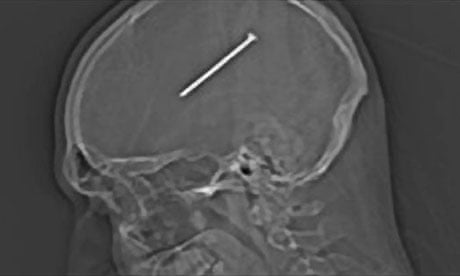

Si vous avez lu mon infographie #1, vous devez avoir compris qu’on pouvait avoir de la douleur sans dommage. Il est fréquent également de voir des dommages sans douleur, c’est le cas par exemple des signes d’imagerie dont j’ai déjà un peu parlé ici même si on peut les interpréter comme des cicatrices ou des rides plus que comme des dommages. Il y a également beaucoup d’histoires de gros dégâts sans douleur. L’histoire de Dante Autullo en est un exemple parmi beaucoup d’autres. Cet homme avait mal tiré avec son pistolet a clou et s’est retrouvé blessé à la tête. Il pensait que c’était une égratignure et n’a accepté d’aller à l’hôpital que le lendemain matin parce qu’il se sentait nauséeux. Il avait en fait un clou dans le cerveau.